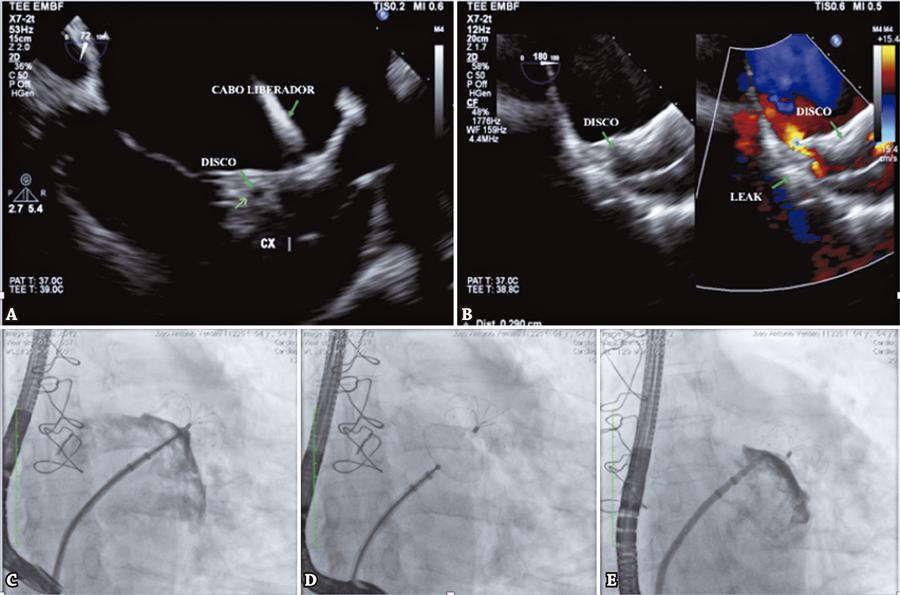

Figura 3

Imagens do ecocardiograma transesofágico e da fluoroscopia pré e pós-liberação dispositivo LAmbre™ no apêndice atrial esquerdo.